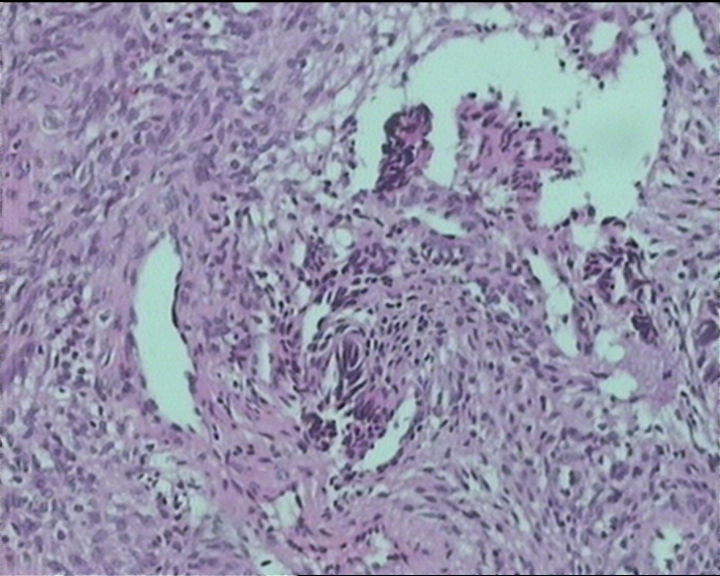

54岁女性,临床“宫颈息肉”送检;巨检:组织一块1。5*1CM,灰红。

Sternberg病理学上诊断宫颈原位腺癌的标准是腺体的上皮去粘液分化,呈乳头状或筛网状增生,核分裂易见,这例显然达不到此标准。此例还是归入到腺上皮不典型增生为好。

It is benign. Benign endocervical polyp with tubal metaplasia.

输卵管粘膜化生

细胞及腺体均有异形,图6、11、16象有纤维间质反应,考虑高级别上皮内瘤变/原位癌,腺癌不能除外。